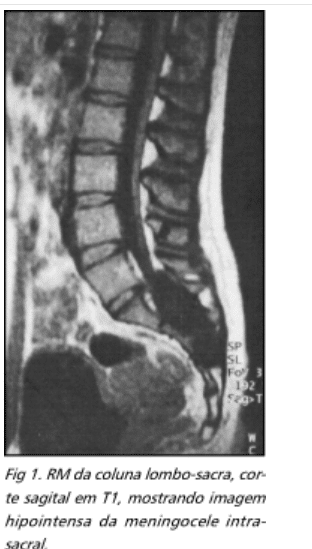

- FRANCO, Gláucio Mendes; LOPES, Humberto; PIRES, Leopoldo Antônio; SOUZA, Sérgio Franca de; PINTO, Moisés Pereira; MARIZ, Fernando Eduardo; CORDEIRO, Anderson Finotti. Meningocele intra-sacral oculta: relato de caso. Occult intrasacal meningocele: case report.

- Meningocele e mielomeningocele: esses defeitos do tubo neural, caracterizados pela protrusão das meninges (no caso da meningocele) ou da medula espinhal (no caso da mielomeningocele) através de uma abertura na coluna, são claramente visíveis na RM, que mostra o conteúdo do saco protuberante bem como a extensão da herniação.

- Meningocele: herniação das meninges através de um defeito na coluna vertebral